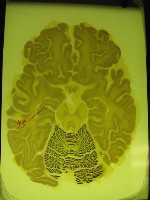

Hasta ahora, un cerebro muerto no era más que un (gran) montón de neuronas que habían dejado de funcionar. Los científicos acostumbran a guardar cerebros o partes de ellos para poder realizar experimentos destinados a conocer mejor su estructura. Todos estos análisis se hacen partiendo de la base de que se está trabajando sobre un trozo de tejido muerto y que este no es capaz de realizar ninguna de las actividades que desarrolla mientras que esta vivo. Sin embargo, puede que estén equivocados. En los últimos días, apareció publicado un artículo en la prestigiosa revista Nature que da cuenta como un grupo de neuronas pertenecientes a la región del hipocampo de una rata fueron capaces de almacenar información durante varios segundos, a pesar de pertenecer a un cerebro muerto y cortado en trocitos.

Es posible guardar y recuperar información de un tejido cerebral almacenado in vitro.El profesor de neurociencia, fisiología y biofísica de la Case Western Reserve University School of Medicine Ben Strowbridge y el estudiante de doctorado Phillip Larimer, lograron por primera vez en la historia guardar y recuperar información de un tejido cerebral almacenado in vitro. Esta es una técnica ampliamente utilizada para realizar experimentos en tubos de ensayos o en un ambiente controlado fuera un organismo vivo. En el caso del trabajo de Strowbridge y Larimer, el tejido pertenecía a la región del cerebro denominada hipocampo, que se sabe se encarga de almacenar los recuerdos. Como parte del experimento, fueron capaces de obtener un patrón de “actividades específicas en determinadas células del cerebro”. Las células en cuestión se conocen como “células de musgo” (mossy cells) y forman parte del hipocampo. “Los neurocientíficos generalmente reconocen tres tipos de memoria: la declarativa, que se usa para recordar hechos o sucesos específicos; la de procedimiento, que sirve para recordar actividades como andar en bicicleta; y la de trabajo, que almacena la información en el corto plazo”, explica Strowbridge. “En este experimento en particular, queríamos saber cuáles eran los circuitos específicos del cerebro que son responsables de la memoria de trabajo.” Utilizando el tejido cerebral de roedores, Strowbridge y sus colegas descubrieron que podían reproducir el funcionamiento de la memoria a través de la estimulación mediante electrodos. “El tejido cerebral muerto, aislado del resto del cuerpo, fue capaz de recordar de cuál de los dos electrodos utilizados procedía la estimulación”, explica Strowbridge. “Esta información permaneció almacenada en el tejido durante 10 segundos, el mismo tiempo que se almacena naturalmente en los mamíferos, incluyendo seres humanos.”

Las células en cuestión forman parte del hipocampo.Strowbridge dice que “no es posible almacenar información en una sola célula, pero utilizando un trozo de cerebro realmente es posible implantar recuerdos” en un tejido muerto. Los experimentos, como imaginaras, recién comienzan. Es muy posible que esto solo “funcione” en regiones del tejido cerebral muy específicos- como el hipocampo y que hayan muerto muy recientemente. También deben ser conservados de una manera muy específica. Es difícil predecir qué tipo de aplicación puede tener un descubrimiento como este, si es que tiene alguna. Pero no deja de ser curioso que el cerebro, aún muerto, pueda realizar alguna de sus funciones elementales.